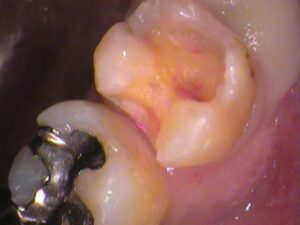

治療を始めていきます。

銀歯を削り取って外してみると、

このような状態でした。

接着剤の汚れを取っていくと、

歯の中に白いものが。

セメントといってお薬で以前の治療で詰めてありました。

虫歯が大きく深い箇所に神経を保護するようにセメントが詰められます。

以前の古いセメントも削り取って歯の内部を確認します。

う蝕検知液という、虫歯を染色するお薬をつけてみると、

手前の歯との間の所が赤く染まっています。

レントゲン写真で銀歯の隙間が黒くなっていたところですね。

やはり虫歯がありました。